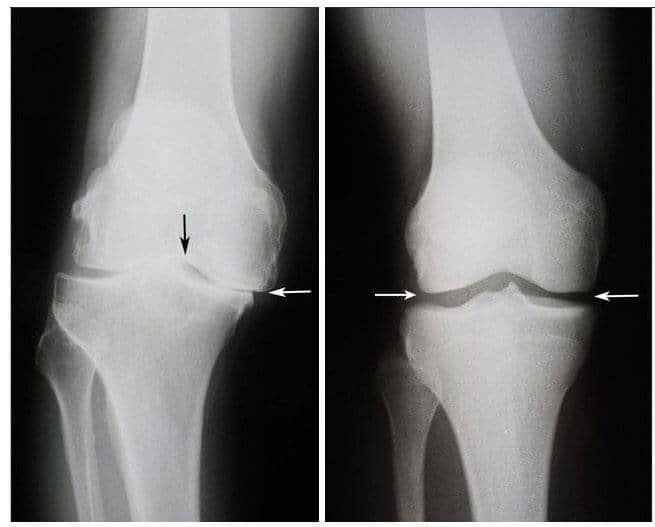

Stânga: radiografia genunchiului drept al dnei Bogza la 75 de ani.

Țesutul cartilaginos este practic complet distrus. Recomandările medicilor - înlocuirea articulației

cu o proteză.

Dreapta: radiografia articulației genunchiului drept al dnei Bogza după curs

cu produsul „Steplex".